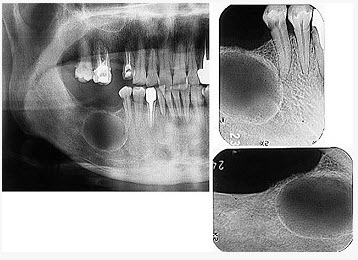

发现下前牙变色,唇侧牙龈一肿物一月余,经X线检查,结果如图。最可能的诊断是()

A、根尖囊肿

B、牙龈瘤

C、根尖脓肿

D、成釉细胞瘤

E、牙骨质瘤

A